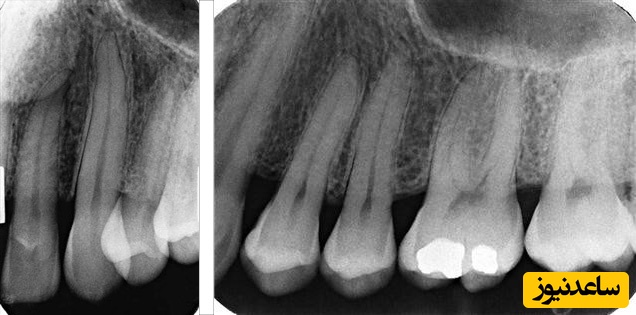

به گزارش سرویس سلامت ساعدنیوز، با عکس رادیوگرافی می توان فساد و پوسیدگی دندان را حتی زمانی که مینا هنوز سالم به نظر می آید، تشخیص داد، به ویژه وقتی پوسیدگی بین دندان ها مخفی شده یا زیر خط لثه باشد. عکس رادیوگرافی به تشخیص آبسه دندان، آسیب استخوان ناشی از بیماری پیر دندانی، شکستگی های فک و دندان سایر ناهنجاری های فک و دندان نیز کمک می کند. به علاوه، اطلاعاتی در زمینه دندان های درنیامده یا گیرکرده، در اختیار دندان پزشکان می گذارد.

یافتن مشکلات دهانی مانند پوسیدگی دندان ، ساختارهای دندانی پنهان (مانند دندان عقل) و آسیب به استخوان های که از دندان حمایت می کنند (مانند ریشه های شکسته دندان). اشعه ایکس دندانپزشکی اغلب برای یافتن مشکلات اولیه حتی قبل از بروز هرنوع علائمی بکار می روند.

دندانپزشکان بدون عکسبرداری با اشعه ایکس ممکن است متوجه مراحل ابتدایی پوسیدگی دندان نشوند.

رادیوگرافی دندان پری اپیکال: این روش برای نمایش دادن تمامی دندان ها اعم از تاج و فک فوقانی استفاده می شود. به طوری که هر گونه تغییرات غیر معمول در ریشه و تمامی ساختار های استخوانی به طور واضح در صفحه مانیتور نمایش داده می شوند.